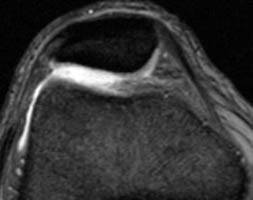

A condromalácia de patela consiste no “amolecimento” da cartilagem da patela.

A condromalácia pode variar desde amolecimento da cartilagem até uma lesão profunda atingindo toda a espessura da cartilagem da patela.

A cartilagem da patela é espessa com aproximadamente 7mm, sendo a cartilagem mais espessa do corpo humano.